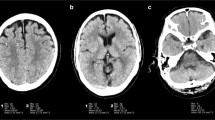

Accelerated MPRAGE reduced scan times by 38% compared to C-MPRAGE (142 s vs. 320 s). For quantitative error metrics, DNN showed better performance than GRAPPA and E-SPIRIT (p < 0.001). For qualitative evaluation, overall image quality of DNN-MPRAGE was comparable (p > 0.999) or better (p = 0.025) than C-MPRAGE, depending on the reader. Pixelation was reduced in DNN-MPRAGE (p < 0.001). Other qualitative parameters were comparable (p > 0.05). Lesions in C-MPRAGE and DNN-MPRAGE showed good agreement for the dice similarity coefficient (= 0.68) and linear regression (R2 = 0.97; p < 0.001).

• DNN-MPRAGE outperformed conventional reconstruction on accelerated scans (SSIM of DNN-MPRAGE = 0.96, GRAPPA = 0.43, E-SPIRIT = 0.88; p < 0.001).

• Compared to C-MPRAGE scans, DNN-MPRAGE showed improved mean scores for overall image quality (2.46 vs. 2.52; p < 0.001) or comparable perceived SNR (2.56 vs. 2.58; p = 0.08).